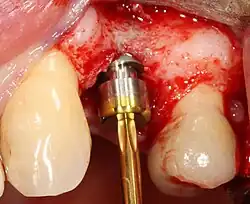

Most implant systems have five basic steps for placement of each implant:[28]: 214–221

- Soft tissue reflection: An incision is made over the crest of bone, splitting the thicker attached gingiva roughly in half so that the final implant will have a thick band of tissue around it. The edges of tissue, each referred to as a flap, are pushed back to expose the bone. Flapless surgery is an alternate technique, where a small punch of tissue (the diameter of the implant) is removed for implant placement rather than raising flaps.

- Drilling at high speed: After reflecting the soft tissue, and using a surgical guide or stent as necessary, pilot holes are placed with precision drills at highly regulated speed to prevent burning or pressure necrosis of the bone.

- Drilling at low speed: The pilot hole is expanded by using progressively wider drills (typically between three and seven successive drilling steps, depending on implant width and length). Care is taken not to damage the osteoblast or bone cells by overheating. A cooling saline or water spray keeps the temperature low.

- Placement of the implant: The implant screw is placed and can be self-tapping;[50]: 100–102 otherwise, the prepared site is tapped with an implant analog. It is then screwed into place with a torque controlled wrench[54] at a precise torque so as not to overload the surrounding bone (overloaded bone can die, a condition called osteonecrosis, which may lead to failure of the implant to fully integrate or bond with the jawbone).